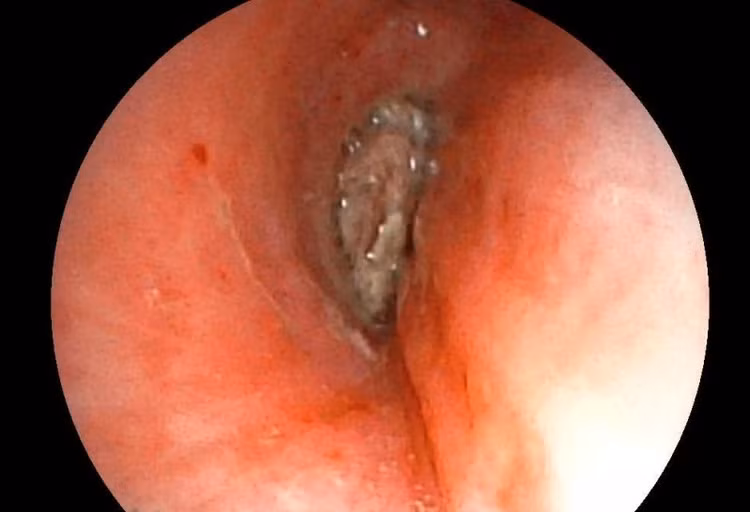

Ê-kíp của bác sĩ CKI Phạm Thị Út Trang – Phó Trưởng Khoa Nội hô hấp đã phối hợp với bác sĩ gây mê hồi sức đã nhanh chóng tiến hành nội soi phế quản ống mềm, phát hiện dị vật góc cạnh khoảng 1cm là hạt kha tử hình bầu dục, bề mặt trơn nhẵn, hai đầu nhọn nằm chắn, gây bít tắc trong lòng phế quản gốc phải, ngay sát vị trí chia nhánh phế quản phân thùy - khu vực giải phẫu hẹp, góc rẽ nhánh phức tạp khiến việc gắp dị vật gặp khó khăn. Ê-kíp nội soi can thiệp đã khéo léo tiếp cận và thành công gắp dị vật ra khỏi lòng phế quản bệnh nhân. Sau can thiệp, sức khỏe của bệnh nhân ổn định, thở dễ dàng, không còn cảm giác tức ngực, được xuất viện sau 24h theo dõi.

Hình ảnh dị vật góc cạnh khoảng 1cm là hạt kha tử hình bầu dục, gây bít tắc trong lòng phế quản. Ảnh BV